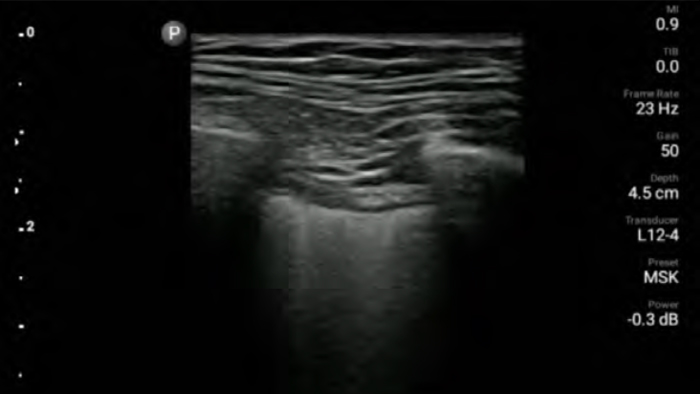

Ultraschall am Patientenbett

Lumify kann am Patientenbett ein wertvolles Hilfsmittel sein, um den Status des Mageninhalts zu ermitteln und das Risiko einer Lungenaspiration zu senken. Dadurch lässt sich wiederum mitunter das Risiko von Anästhesiekomplikationen reduzieren.